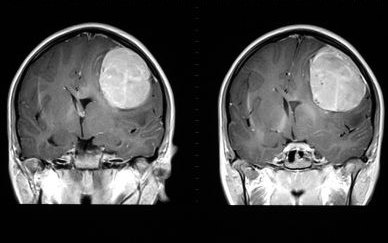

주로 사용하는 뇌에 종양이 생겼을 때는 증상이 세게 오지만, 주로 사용하지 않는 뇌에 종양이 생기면 별 증상이 없을 수 있다. 예를 들어 우측 전두엽에 6cm짜리 종양이 있을 때, 환자의 '우성반구'가 좌뇌이면 별 증상이 없을 수 있다. 반면 우성반구가 우뇌이면 이 환자에게 증상이 아주 세게 올 수 있다.

우성반구에 종양이 생기면 조그마한 크기일 때도 증상이 나타나 조기 발견해 잘 치료되는 경우가 있다. 반면, 우성반구가 아닌 뇌에 종양이 생겨서 증상이 8cm짜리가 돼서야 처음 나타난 환자는 수술 받기 어려울 수도 있다. 종양의 크기가 클수록 수술이 어렵기 때문에, 늦게 발견되면 치료가 쉽지 않다.